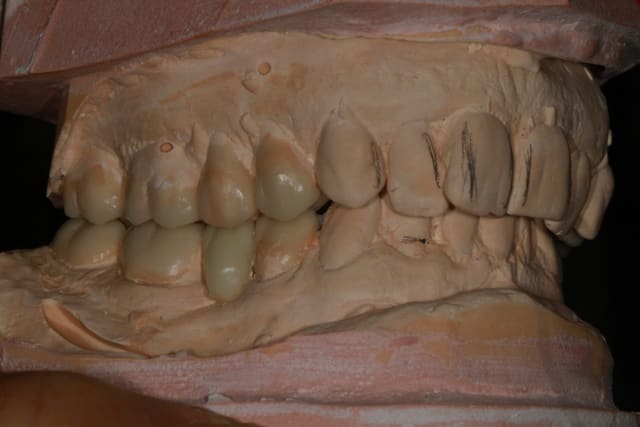

donc dans un premier temps détartrage, détartrage, détartrage Wax up, ....surfaçage couronne , amalgame à la benne taille des postérieurs inférieure et pose de provisoires pour valider la nouvelle DV.

Wax up et taille crayon...

Empreinte, détourage et préparation des cires avec une occlusion différente de celle du wax up, un peu plus de DV

Le trait rouge sur les incisive donne à peu de chose prêt l'origine...